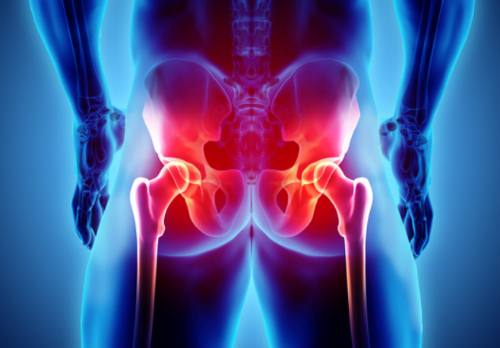

고관절 통증은 고관절과 관련된 관절 통증으로 정의됩니다. 이 관절은 상체에서 체중을 분산시키는 역할을 담당하며, 걷거나 뛸 때에는 체중의 약 3배나 10배가량의 부하를 견딥니다. 다른 관절과 마찬가지로 충격이나 체중 변화가 고관절 통증 증상을 유발할 수 있습니다. 이러한 통증 증상을 일으키는 주요 질환으로는 퇴행성 고관절염, 대퇴골 골절 그리고 선천성 고관절 탈구 등이 있습니다.

고관절은 골반과 대퇴골의 대퇴골두가 만나는 관절로, 상체와 하체를 연결하는 중요한 부위입니다. 이 관절은 서 있거나 앉아 있을 때부터 평소 일상생활에서 빈번하게 활용되는데, 이로 인해 상당한 부담을 견뎌내야 합니다. 고관절은 탁구공과 비슷한 크기와 모양을 가진 대퇴골두가 지탱하는데, 걸을 때 고관절에 가해지는 무게는 체중의 3~4.5배까지 증가하며 만약 계단을 오를 때는 대퇴골두가 체중의 8배에 달하는 부담을 견뎌야 하므로, 고관절은 상당한 스트레스와 손상의 위험에 노출될 수 있습니다.